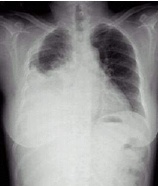

| 病史:女性,76岁,胸闷伴呼吸困难6天,不能平卧1天。诊断: |

| ○右侧胸腔积液 | |

| ○右下肺不张 | |

| ○右下胸膜肥厚 | |

| ○大叶肺炎 | |

| ○气胸 |